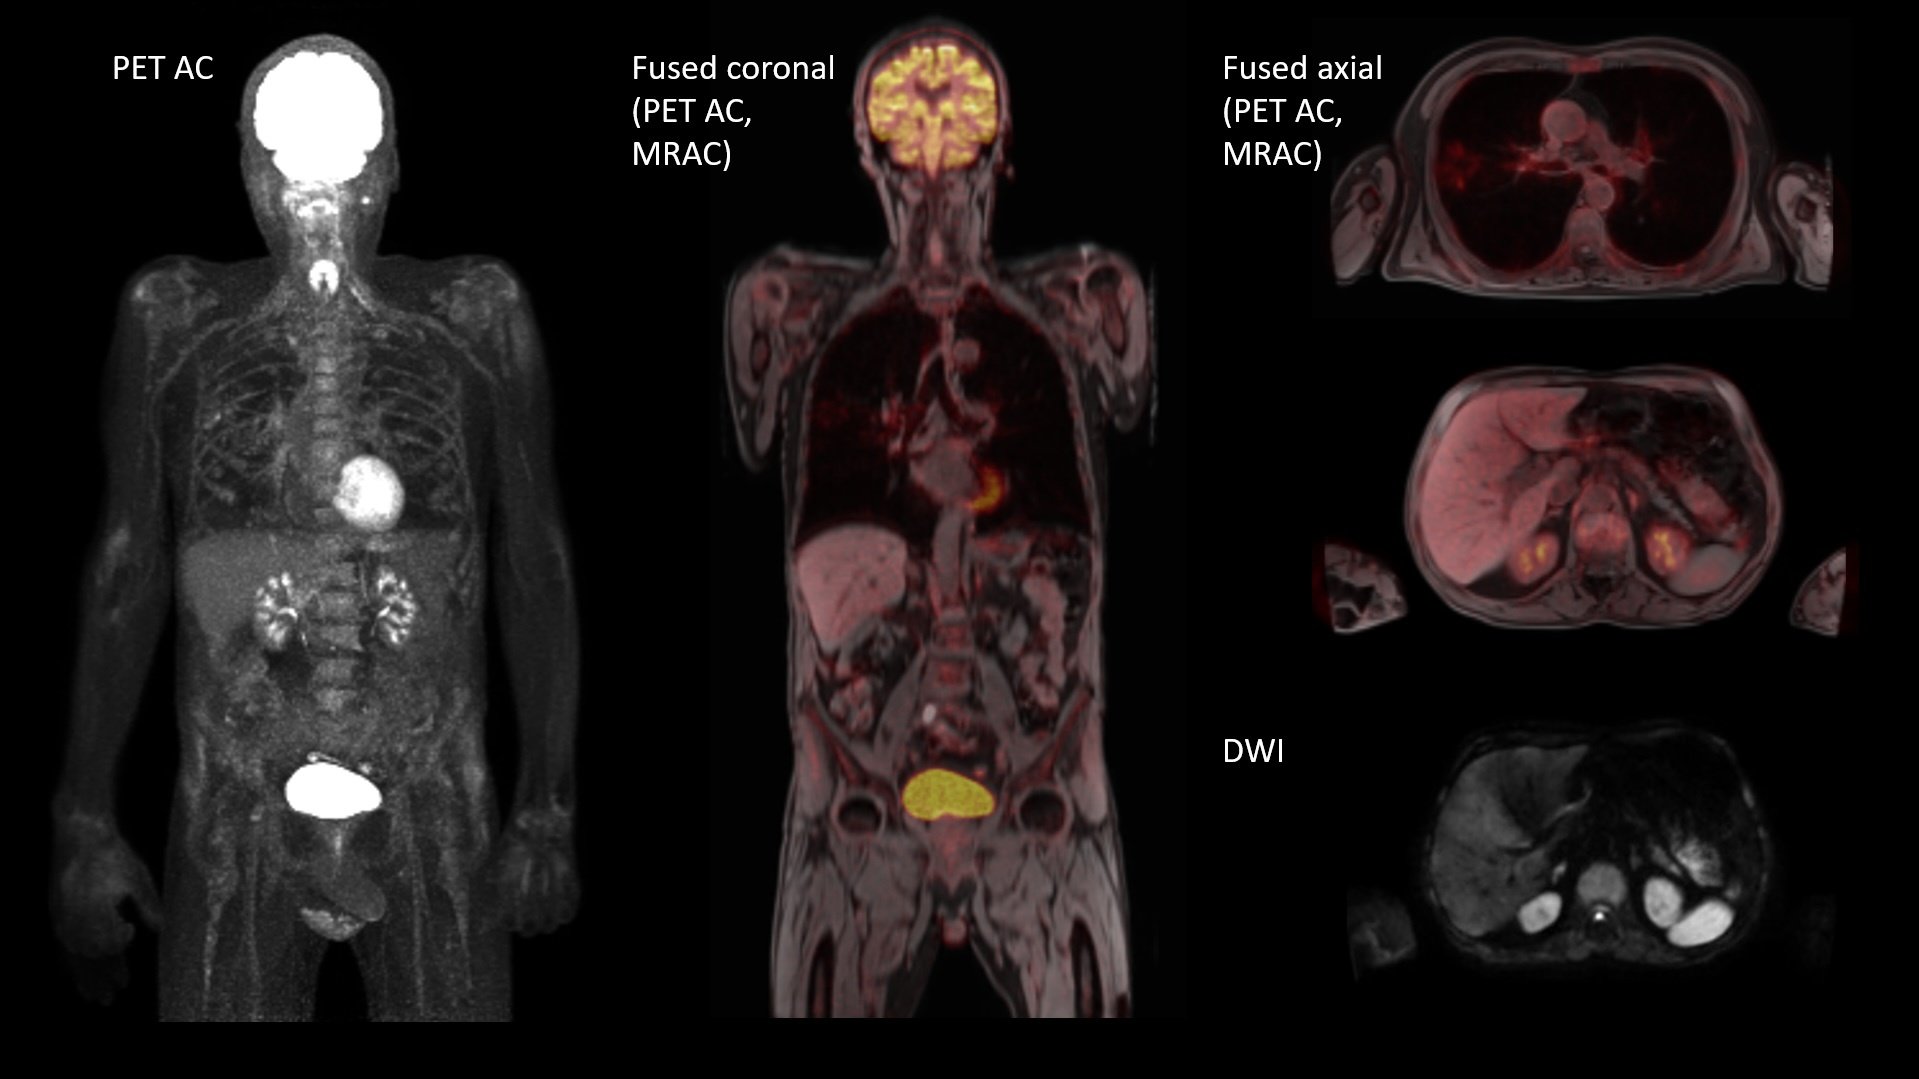

Follow up PET/MR images show complete regression of follicular lymphoma after 15 months post immunotherapy.

• 75-year-old male patient, 62kg

• Injected dose: 184 MBq i.v.

• Uptake time: 79 min p.i.

• Sequences: MRAC (VIBE-DIXON), DWI

• MR TA: 5:40 min (1:25 min per bed)

• PET TA: 20 min (5 min per bed) 7

• Total scan range: 110 cm (4 beds)

Study-ID: 2aaaa3340 | Image courtesy of RIGS Hospital, Copenhagen, Denmark